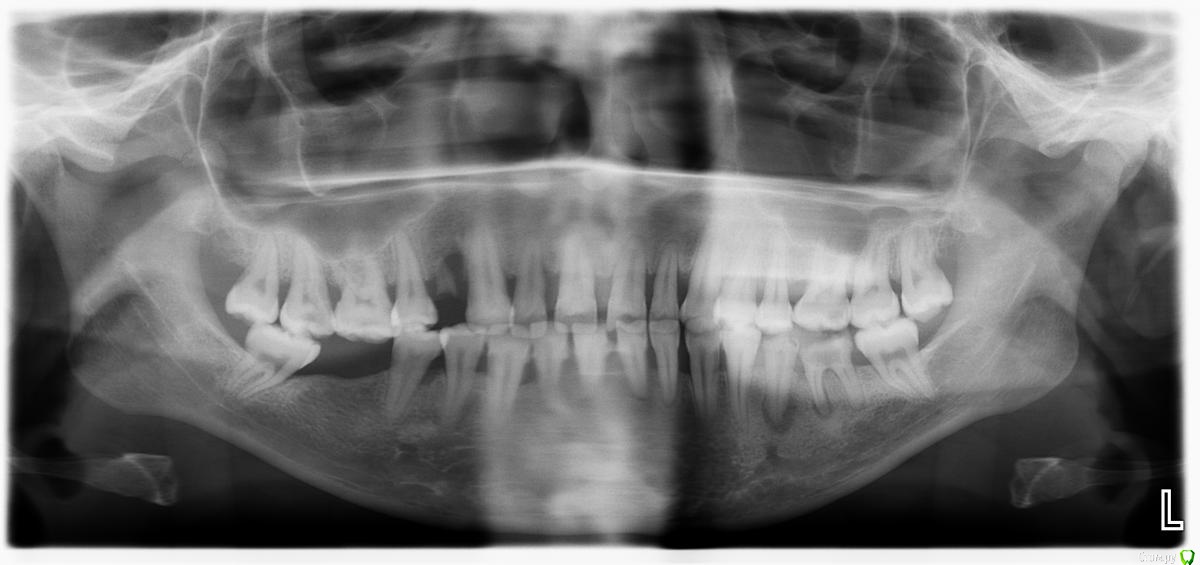

Денис777 Опубликовано 2 февраля, 2015 Автор Поделиться Опубликовано 2 февраля, 2015 Пациент пришел по поводу эстетического не удовлетворения своих зубов. Вееро образное расхождение фронтальных зубов,подвижность 2 степени.Нужен совет докторов кто как борется с пародонтозом,протокол лечения.P.S Извиняюсь за фото не было времени перекинуть в электронном ввиде Ссылка на комментарий

Денис777 Опубликовано 4 февраля, 2015 Автор Поделиться Опубликовано 4 февраля, 2015 (изменено) Вот Доктора!!!Вчера получилось сделать фото и скинуть нормальное орто.. Изменено 4 февраля, 2015 пользователем Денис777 Ссылка на комментарий

krokomot Опубликовано 17 февраля, 2015 Поделиться Опубликовано 17 февраля, 2015 (изменено) Вариантов много, на что настроена сам пациентка, просто терапию и ли по полной программе голивуд? Из этого и вытекает бюджет. Учитывая узуру от поедания семечек он довольно скромный. Нужны все специалисты терапевты, хирурги, ортопеды( вряли она наденет бреккеты, а без них зубы обратно не задвинешь). Лечение каналов зубов с апекальным переодонтитом, удаление зубов со значительной атрофией. Протезирование боковых и фронтального отделов + конечно же регулярная переодонтальная поддерживающая терапия. Так получится что-то более менее вменяемое, за что стыдно не будет Изменено 17 февраля, 2015 пользователем krokomot Ссылка на комментарий